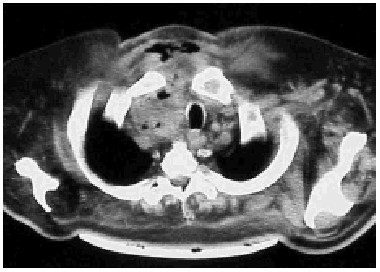

During the study period we treated 26 cases (20 men and 6 women) for acute mediastinitis. The mean age of the patients was 55 years (range 2685 years). In 17 cases (64%) mediastinitis originated in the esophagus: 8 (30%) occurred after resection of esophageal carcinoma and 9 (34%) were secondary to esophageal perforation. Four of the perforations were due to spontaneous rupture (Boerhaave syndrome), 4 were iatrogenic, and 1 was caused by ingestion of a foreign body (a lamb bone). In 6 cases (23%), the cause was oropharyngeal infection due to dental or peritonsillar abscess (Figure), and 3 cases (12%) were secondary to median sternotomy wound infection. Mediastinitis was associated with pleural empyema in 20 cases (76.9%) and with peritonitis in 1 case (3.5%). All diagnoses were confirmed by computed axial tomography. In the cases with infection originating in the esophagus, contrast-enhanced images were obtained to locate the perforation site. Diagnosis was reached within 12 hours in 15 cases (56.7%) and within 24 hours in 8 (30.8%). Diagnosis and, therefore, treatment were delayed for the remaining three patients (12.5%). All the patients underwent thoracotomy except one who was treated by means of chest tube drainage. In addition to mediastinal debridement and drainage, 10 patients underwent esophagectomies or resection of the esophago-gastric reconstruction (deferring a new reconstruction), 5 received primary sutures of the esophagus covered with an intercostal muscle or pericardial fat flap, 1 was reconstructed with a greater pectoral muscle flap, and 1 underwent sternectomy plus intrathoracic omental transposition. The patients required a mean 3.33 (range 25) surgical procedures in separate operations not counting deferred reconstructions. Four patients (15.4%) died: 2 in relation to esophageal disease and 2 with descending necrotizing mediastinitis. Postoperative complications are summarized in Table 1.

Figure. Mediastinitis due to oropharyngeal infection. Cervical subcutaneous emphysema and purulent secretions in the right paratracheal region.